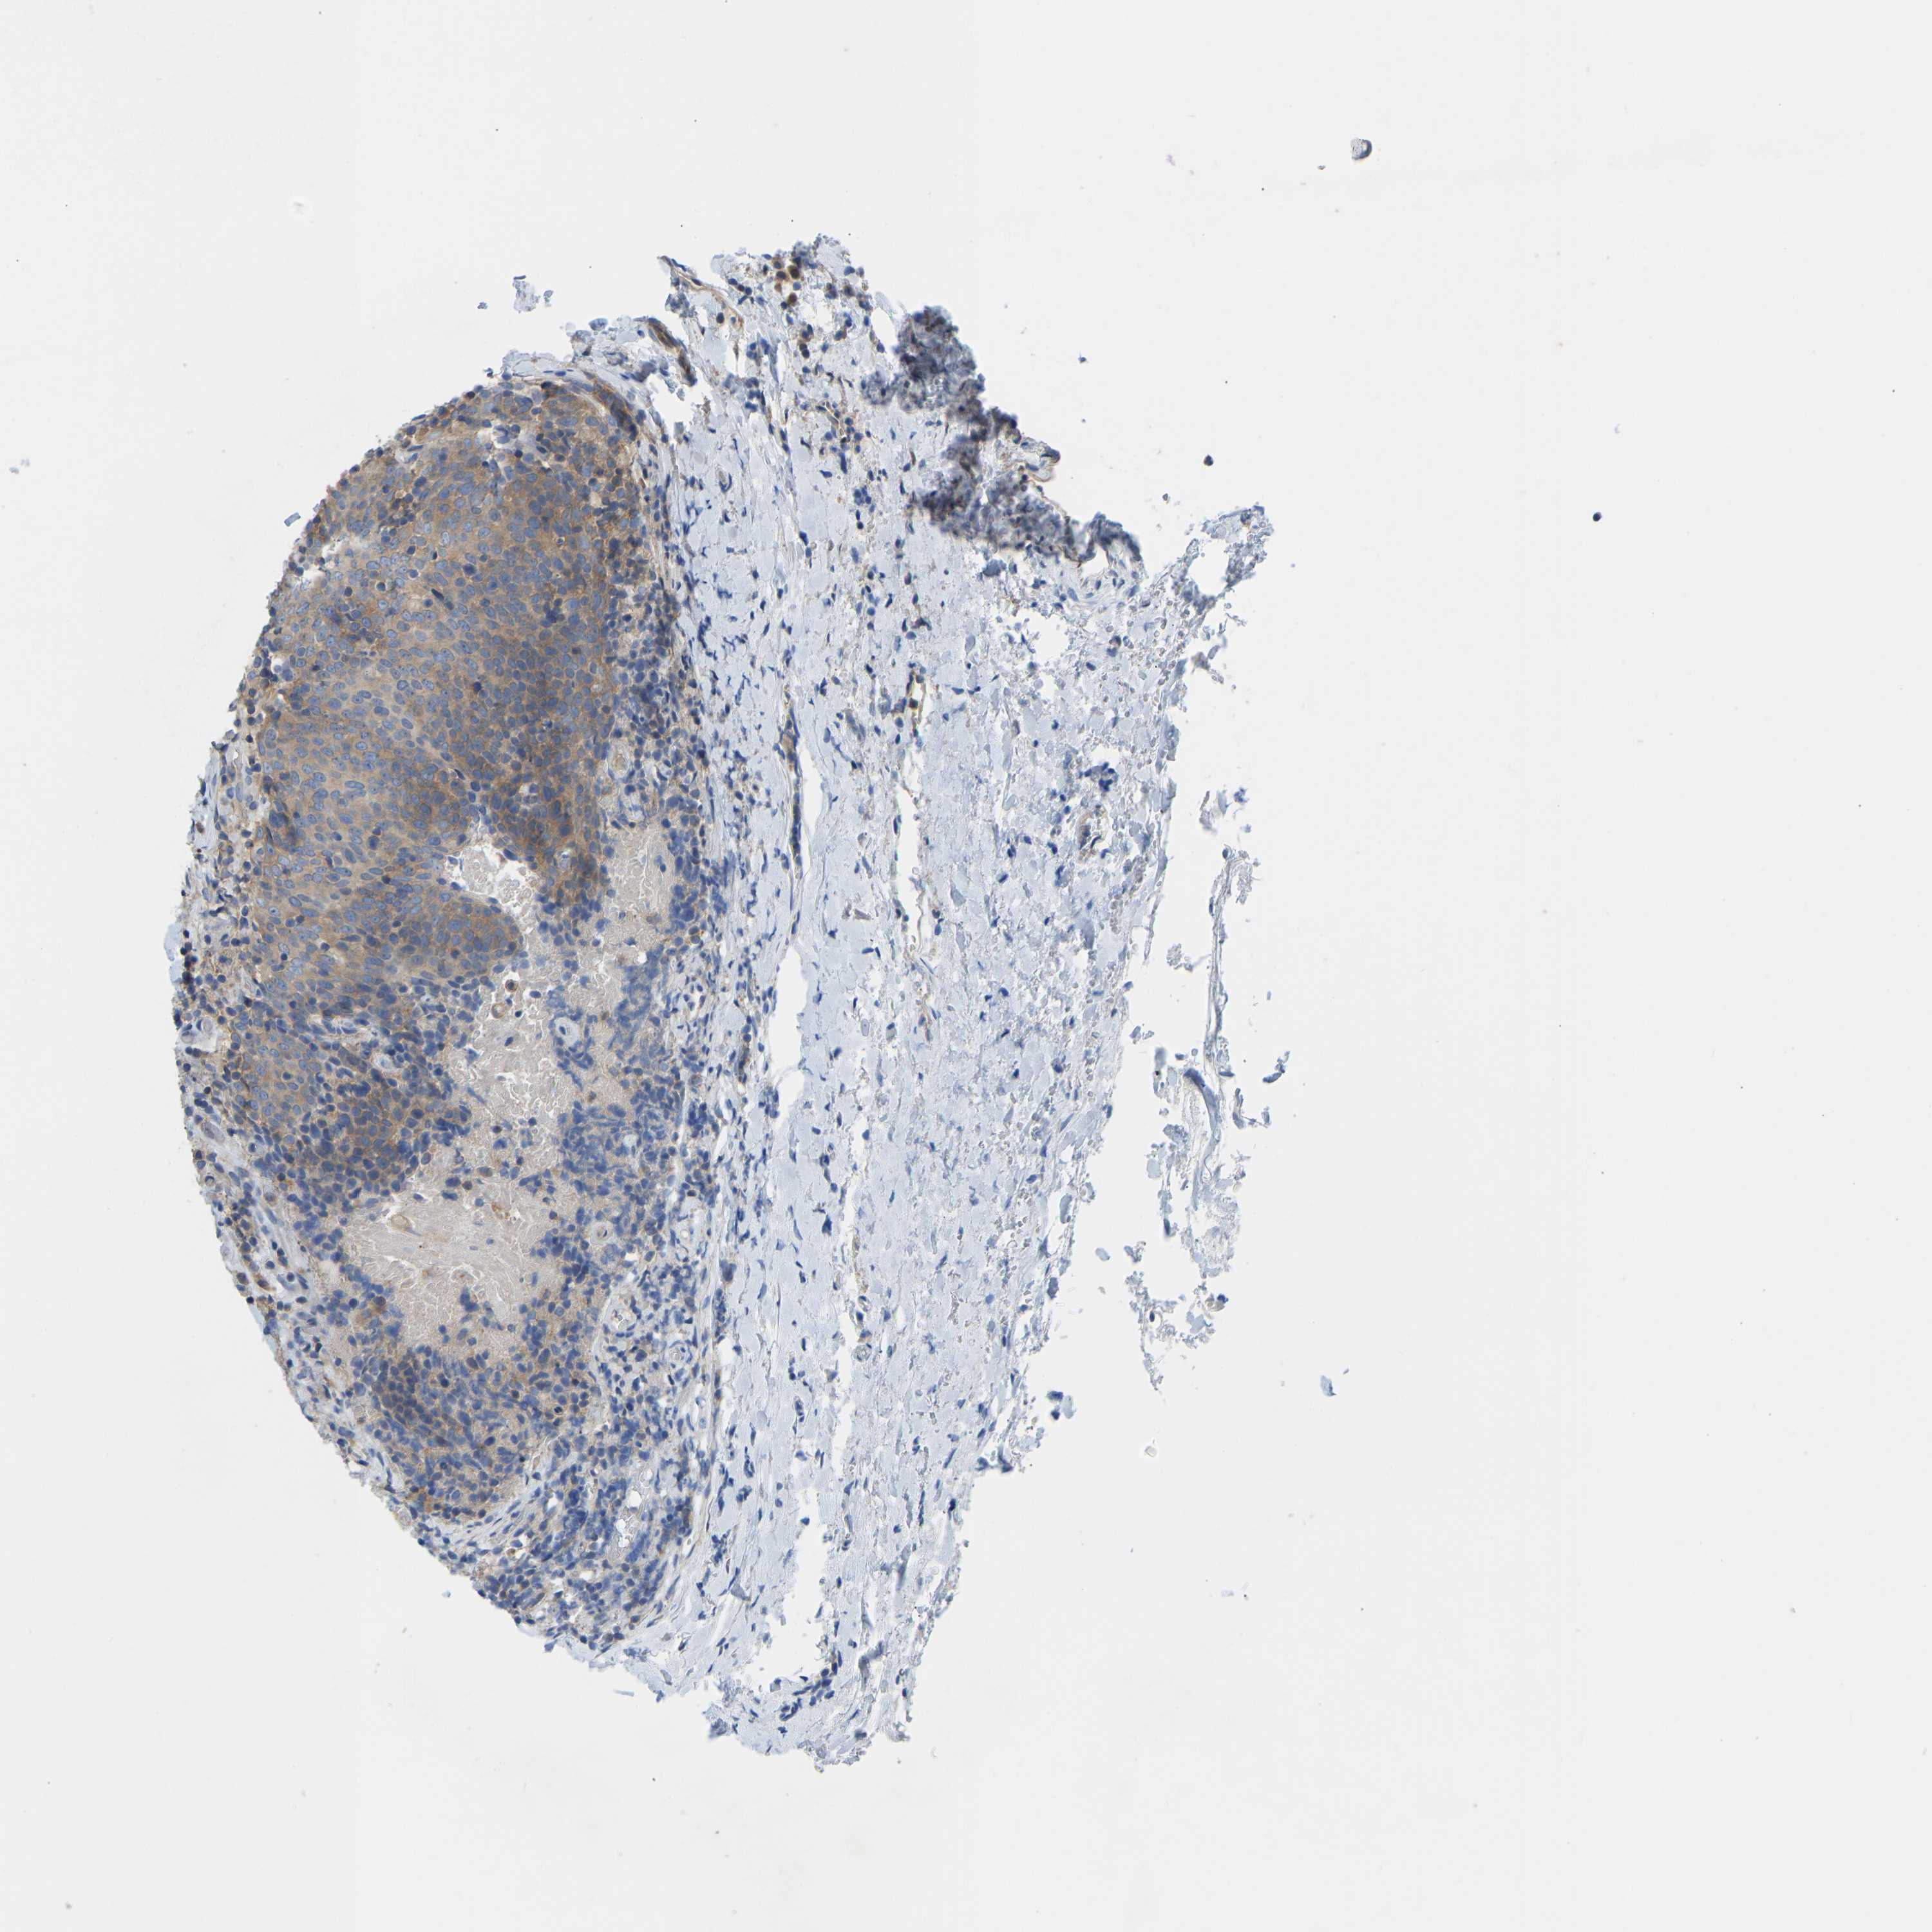

HEAD AND NECK CANCER - Protein expressioni

A mouse-over function shows sample information and annotation data. Click on an image to view it in a full screen mode. Samples can be filtered based on level of antibody staining by selecting one or several of the following categories: high, medium, low and not detected. The assay and annotation is described here.

Antibody stainingi

Antibody staining in the annotated cell types in the current human tissue is reported as not detected, low, medium, or high, based on conventional immunohistochemistry profiling in selected tissues. This score is based on the combination of the staining intensity and fraction of stained cells.

Each image is clickable and will lead to virtual microscopy that enables deeper exploration of all samples and also displays staining intensity scores, fraction scores and subcellular localization as well as patient and tissue information for each sample.

Antibody HPA012778

Antibody CAB018581

Staining

High

Medium

Low

Not detected

Intensity

Strong

Moderate

Weak

Negative

Quantity

>75%

75%-25%

<25%

None

Location

Nuclear

Cytoplasmic/membranous

Cytoplasmic/membranous,nuclear

Squamous cell carcinoma, NOS

Squamous cell carcinoma, metastatic, NOS

Adenocarcinoma, NOS